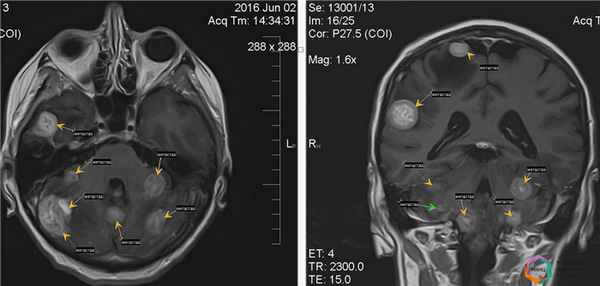

Рис.1 МРТ без контрастного усиления. Картина внешне не измененного мозгаРис. 2 МРТ с контрастным усилением. Картина тотального метастатического поражения

Клинический пример №2

Пациентка К., 61 года, обратилась в кабинет магнитно-резонансной томографии по поводу исследования головного мозга, беспокоят головные боли.

В анамнезе рак молочной железы, операция по поводу удаления образования не проведена, идёт диагностический поиск метастатического поражения других органов.

При проведении магнитно-резонансной томографии в различных режимах и трёх проекциях с применением внутривенного контрастного усиления выявлено множественное метастатическое поражение головного мозга с наличием зон перифокального отёка.

Помимо метастазов очевидных при нативном (бесконтрастном) сканировании, при внутривенном контрастном усилении выявляются дополнительные очаги метастатического поражения головного мозга более малых размеров, не визуализируемых ранее.

Благодаря проведению МРТ в данных двух примерах удалось определить точную причину головных болей, головокружения и шаткости походки, с максимальной точностью определить количество очагов, локализацию метастатического процесса и его распространенность, а также при помощи контрастного усиления выявить метастазы, не визуализируемые при бесконтрастном сканировании, что в дальнейшем определило тактику лечения данного заболевания.